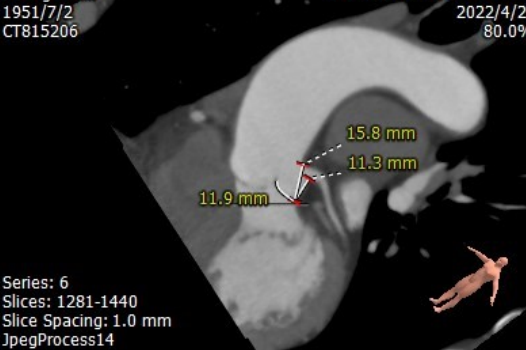

CT评估

图片

主动脉根部CT测量

左冠高度:11.1mm

右冠高度:15.9mm